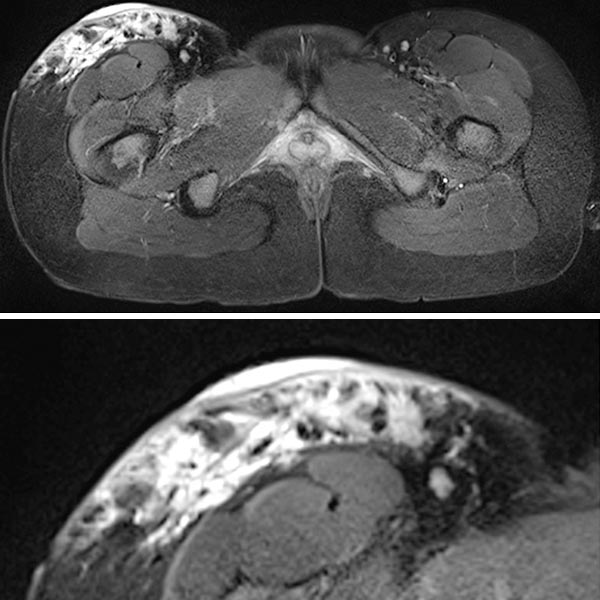

In der koronaren T2-gewichteten, fettunterdrückten MRT auf Höhe des proximalen Oberschenkels ist die lymphatische Malformation aufgrund der enthaltenen interstitiellen Flüssigkeit (Lymphe) stark hyperintens und netzartig verteilt.

Gleiche MRT-Schicht in der nativen T1-Wichtung zeigt die LM hypointens im hyperintensen subkutanen Fettgewebe, entsprechend der enthaltenen Lymphflüssigkeit.

In der transversalen T2-Wichtung, fettunterdrückt, ist die rein epifasziale Ausdehnung der LM im subkutanen Fettgewebe klar zu erkennen. Die darunter liegende Muskulatur ist nicht betroffen.

Beachte in der Ausschnittsvergrößerung (unteres Bild) die exophytische Ausdehnung der mikrozystischen Anteile (stark hyperintens) der LM bis über das Niveau der Haut.

In der gleichen Schichtführung der MRT (oben Übersicht, unten Ausschnittsvergrößerung) in T2-Wichtung ohne Fettunterdrückung sind die gleichzeitig vorhandenen bindegewebigen Anteile der hart tastbaren LM als hypointense netzartige Zeichnung besser zu sehen. Beachte wieder den erhabenen exophytischen Anteil oberhalb des Hautniveaus.

In der axialen fettunterdrückten T1-Wichtung nach KM-Gabe (oben Übersicht, unten Ausschnitt) findet sich die stärkste Anreicherung in den kutan gelegenen, expophytischen, mikrozystischen Anteilen in der Haut. Die darunter liegende LM im subkutanen Fettgewebe reichert dagegen kaum an.